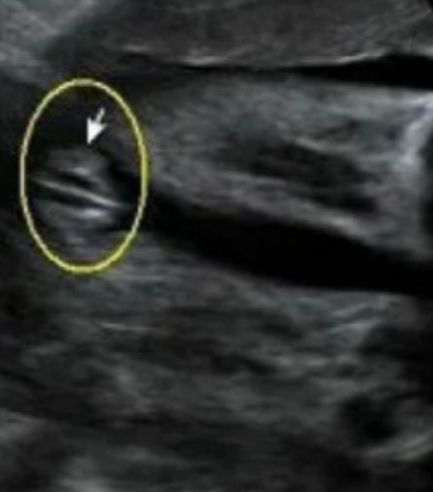

Девочка. Половой бугорок вниз

Результаты скрининга на 12-13 неделе: 80% вероятность девочки. Нужна помощь в сравнении снимков!